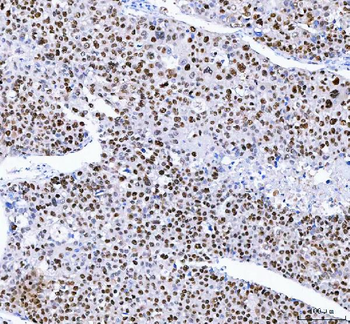

![Anti-FEN1 [SAIC-21C-4]](/images//pub/media/catalog/product/NewWebsite/35/orb1089994_1.png)

![Anti-FEN1 [SAIC-21C-4]](/images/pub/media/catalog/product/NewWebsite/35/orb1089994_2.png)

![Anti-FEN1 [SAIC-21C-4]](/images/pub/media/catalog/product/NewWebsite/35/orb1089994_3.png)